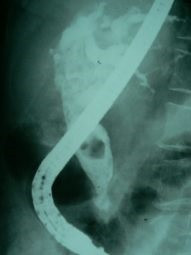

Cálculo gigante ERCP

Envíado por Dr. Carlos Miguel Zavaleta Consuegra